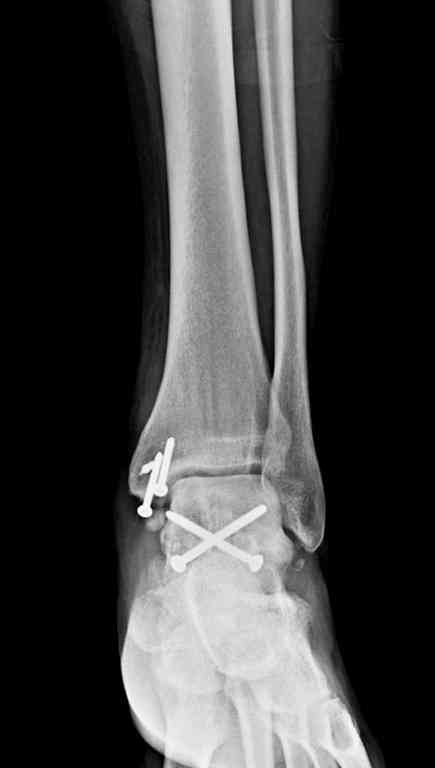

Второй случай прооперирован вчера.

10 дней назад поступил с открытым повреждением медиальной лодыжки и переломо вывихом таранной кости. Ургентно сделана репозиция с наложением наружного фиксатора + Irrigation&Debridment.

Во время репозиции выявили повреждение заднего сухожилия м. тибиалис и задней большеберцовой артерии. Медиальную рану удалось закрыть частично и установлен вакуум.

Дважды провели Irrigation&Debridment с заменой вакуума.

Вчера провели фиксацию.

Из-за многооскольчатости дистальной части малоберцовой, где невозможно было провести фиксацию шурупами, перелом зафиксирован подпирающей пластиной, которая должна служить дополнением отсутствующей дистальной части малоберцовой (lateral cortex substitute).

Для стабильности два шурупа на синдесмоз.

Медиальную рану с приближенными краями продолжаем вакуумировать (KCI). Наружный фиксатор оставлен на пару недель, надеюсь, небольшая рана будет гранулировать и закроется без кожной пластики. Фиксация медиальной ложыжки не планируется.